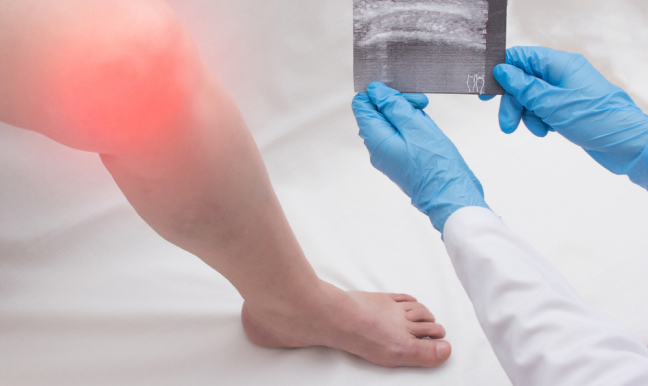

¿Buscas ortopedista en Satélite y alrededores? Soy el Dr. Daniel Machuca. Acude conmigo para ayudarte a recuperar tu salud plena y resolver los siguientes problemas:

¿Buscas resolver un problema de rodilla, cadera o columna? Encuentra traumatólogo en Star Médica. Da clic en el botón y agenda una cita para atenderte.

Libérate de los dolores de columna, cadera o rodilla, acude con un ortopedista y traumatólogo certificado. Soy el Dr. Daniel Machuca, Médico Cirujano con alta especialidad en prótesis de cadera y rodilla.

Recibo a pacientes en Star Médica Lomas Verdes. Tengo experiencia resolviendo desde dolores de rodilla hasta fracturas de cadera, pasando por hernias de disco y ciáticas. Además, tengo subespecialidad en politrauma.

Como traumatólogo en Star Médica, tengo acceso a instrumentos e infraestructura de la más alta calidad para que recuperes el ritmo de tu vida diaria lo más pronto posible.